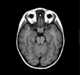

Collateral vessels

In medicine, collateralization, also vessel collateralization and blood vessel collateralization, is the growth of a blood vessel or several blood vessels that serve the same end organ or vascular bed as another blood vessel that cannot adequately supply that end organ or vascular bed sufficiently. Coronary collateralization is considered a normal response to hypoxia and may be induced, under some circumstances, by exercise. [Source: Wikipedia ]